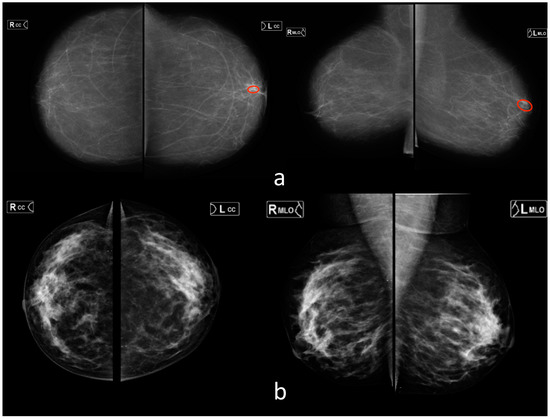

3.3. Mammography (MMG)